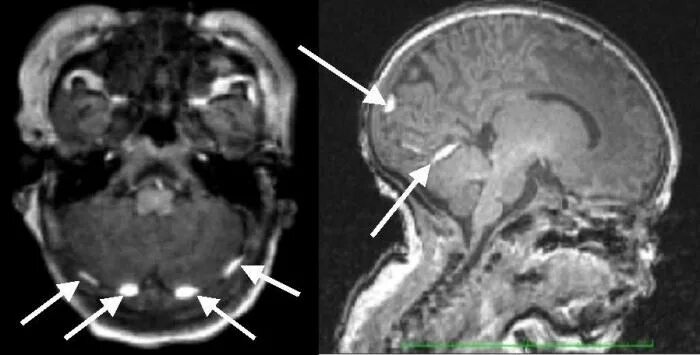

Кровоизлияние в мозг у новорожденного степени